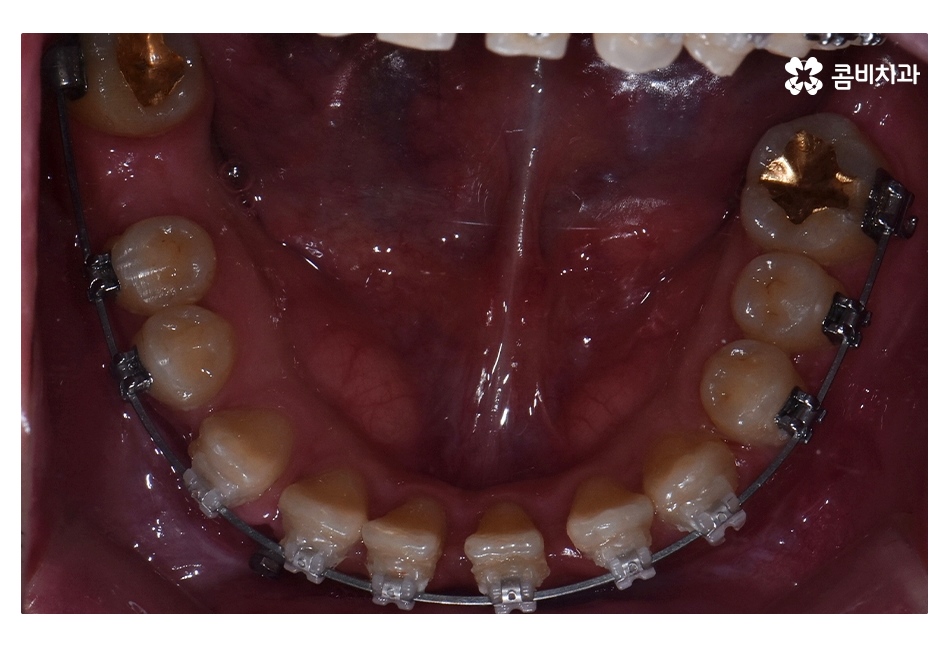

위 환자분의 경우 충치로 인해 오른쪽 아래 제1대구치와

왼쪽아래 제2대구치가 상실된 상태였으며, 치아교정만으로는

치료가 불가능한 케이스였기 때문에 비발치 교정으로

진행하면서 외과수술이 병행된 케이스라고 할 수 있어요

클리피씨교정을 통해서 약 1년 6개월간

치료가 진행이 되었고, 수술과 병행이되며, 치료 마무리 단계에서

임플란트 수술까지 진행이 된 사례라고 볼 수 있는데요.

클리피씨교정이 진행되고 시간이 지날수록 아랫니가

점점 윗니에 덮이는 정상 교합의 상태로 개선되는 것을 볼 수 있는데요.